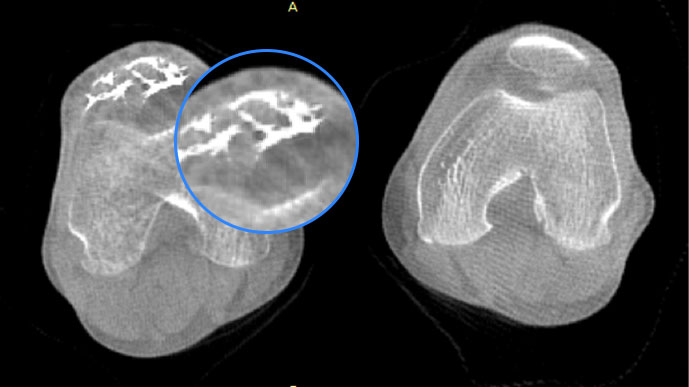

• 膝关节

智能金属伪影抑制算法

关闭金属伪影校正

开启金属伪影校正